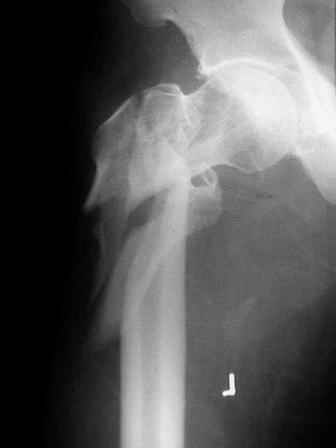

Few days ago I have posted an x-ray of severely comminuted Trochenteric # of Lt. Femur with sub-trochenteric extension of a male patient aged 65 years for opinion of fixation. Eight of you have kindly replied........

I choose Long Gamma Nailing and did it on 24.1.2006.

Now posting the post op x-rays for all of yours comments please. Don't hesitate to criticize me.